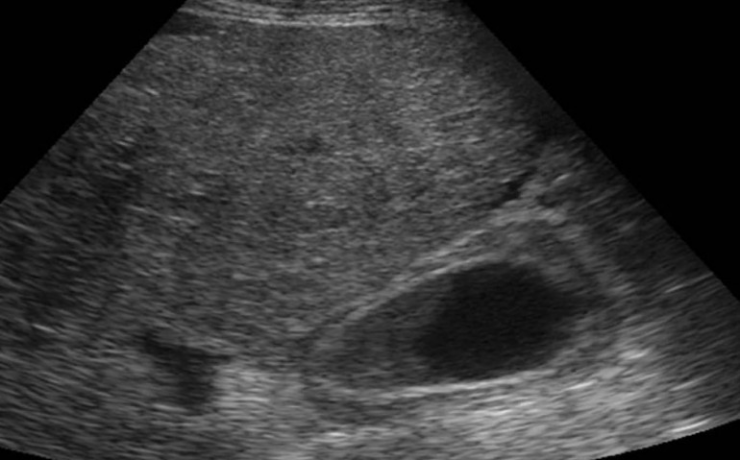

Las neoplasias de la vesícula biliar son una patología poco frecuente, pero es común que lo presenten los pacientes con alguna enfermedad autoinmune, este articulo se trata del reporte de un caso clínico de una paciente de 23 años con el diagnostico de Leiomioma. Los leiomas son tumoraciones benignas de